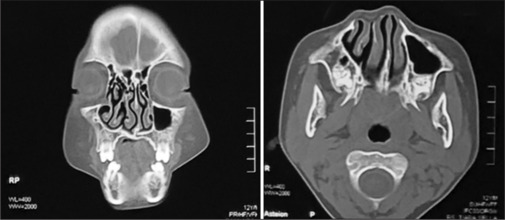

Supernumerary nostril is an extremely rare congenital nasal disorder, with additional nostrils of unknown etiology. The choice of supernumerary nostril reconstruction technique is adjusted to the patient's clinical manifestations. This study evaluated a case of 12-year-old male patient with an additional nostril on the right side of the normal nostril since birth. The patient was diagnosed with a functional supernumerary nostril and treated with nasal reconstruction. Functional supernumerary nostril reconstruction is considered to be functional, cosmetic, and psychosocial development. Internal approach reconstruction was performed using an endoscope to maintain the functional part of the nose, and an external approach reconstruction was performed to form a near-normal nasal morphology. Rhinoplasty outcome evaluation (ROE) can be used to evaluate the patient's psychosocial status after reconstruction procedures.